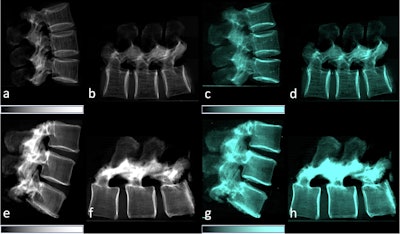

Lateral conventional attenuation (a, b, e, f) and co-registered dark-field (c, d, g, h) images of two spine specimens. Vertical (a, c, e, g) and horizontal (b, d, f, h) scans of the spine specimen of a 77-year-old female with osteoporosis (bone mineral density = 65.75 mg/dL) (a–d) and a non-osteoporotic spine specimen (e–h) of a 61-year-old female (bone mineral density = 169.38 mg/dL).Image available for republishing under Creative Commons license (CC BY 4.0 DEED, Attribution 4.0 International) and courtesy of European Radiology Experimental.